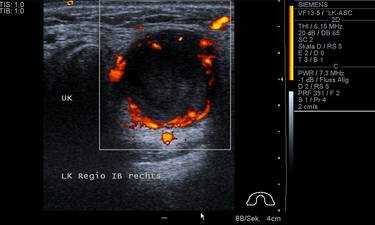

Der Vorteil der Ultraschalluntersuchung gegenüber anderen bildgebenden Verfahren ist die  fehlende Strahlenbelastung sowie die schnelle Verfügbarkeit und Wirtschaftlichkeit. Im Kopf-Hals-Gebiet steht die hohe Auflösung feiner oberflächennaher Strukturen im Vordergrund, die mit modernen Geräten heute schon fast an den mikroskopischen Bereich heranreichen. Klassisches Anwendungsgebiet der Ultraschalluntersuchung ist die Nachsorge bei Tumorpatienten und die Diagnostik von Veränderungen der Speicheldrüsen. Routinemäßig erfolgt zusätzlich die Untersuchung der Schilddrüse, des Mundbodens und der großen Gefäße im Halsbereich.

Eine vollständige Ultraschalluntersuchung und Dokumentation im Kopf- und Halsbereich kann bis zu 30 Minuten dauern. Für krankhafte Veränderungen gibt es momentan kein besseres diagnostisches Verfahren als die Sonographie. Dies gilt umso mehr, je näher der Befund bzw. die Veränderung an der Körperoberfläche gelegen ist. In der Hand des geübten Diagnostikers übertreffen die Ergebnisse der Sonographie die der Computertomographie.